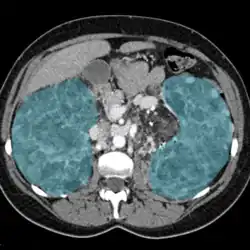

| Enlarged kidneys in blue | |

Nephromegaly is the process whereby one or both kidneys become enlarged. It is defined as an enlargement of more than two standard deviations above the mean for age and body size of a particular individual. It can be caused by a variety of conditions including infiltrative disorders, metabolic conditions, cysts, and other diseases.

Nephromegaly is the process whereby one or both kidneys become enlarged.[2] It is defined as an enlargement of more than two standard deviations above the mean for age and body size of a particular individual. In adults, as the normal kidney length is typically 10–12 cm (3.9–4.7 in), lengths above 13 cm (5.1 in) suggest a general enlargement.[3][4]